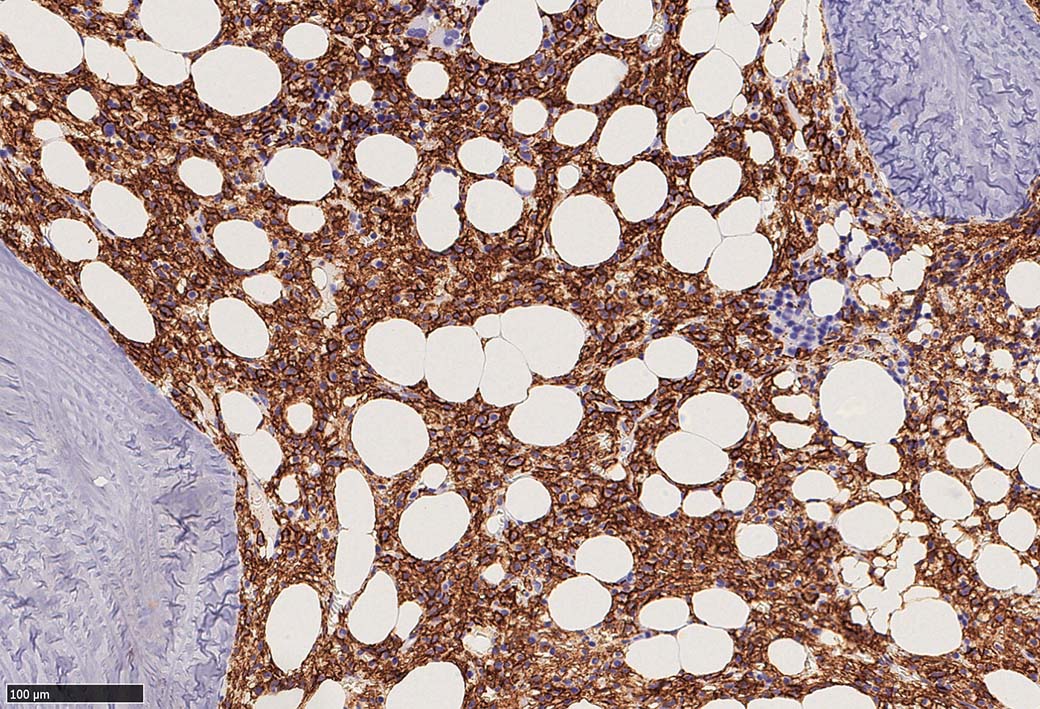

Hairy-FCM のコピー.jpg ASD-up-PAX5ok.jpg びまん性にPAX5陽性の小型B-cellsが増殖している.

増殖細胞はCD20(相変わらずべったり染まる), CD19, PAX5陽性 CD25陽性.

BRAF V600E変異タンパクの免疫染色(山梨医大 大石先生に染色していただきました. ベンタナ, Optiview)